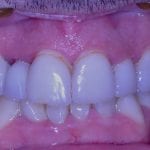

Immediate Post Op